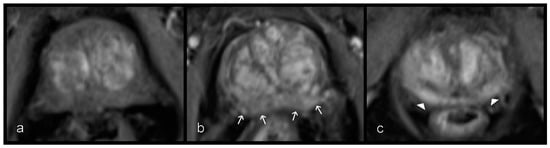

Figure 3.

Inflammatory changes in the peripheral zone from left to right. (a) Stripes (white arrow) and sharp wedges (empty arrowheads), (b) wedges with obscured margins (white arrowheads), and (c) patchy and diffuse signal reduction (empty arrowheads) on T2W sequences.